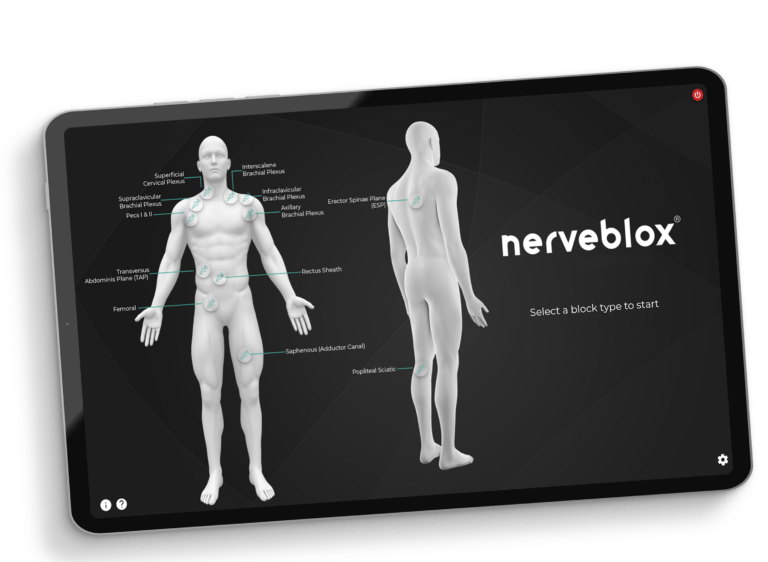

Nerveblox AI technology for ultrasound guidance is meticulously designed for anesthesiologists performing peripheral nerve block procedures and training. It is most valuable for applications requiring precision and those less frequent procedures that can be challenging due to their rarity – areas where AI capabilities outperform human attention. This versatility makes it an indispensable tool for highly skilled anesthesiologists who may require assistance with these uncommon procedures and peace of mind for image interpretation, especially regarding sonoanatomy.

Furthermore, our technology extends beyond anesthesiologists who are experts in ultrasound imaging. Anesthesiologists, including general practitioners, emergency medicine doctors, who may not possess specialized ultrasound training, can harness the power of our AI technology. Nerveblox provides standard, more accurate, and reliable peripheral nerve block guidance for them. This inclusivity ensures that anesthesiologists across all expertise levels can provide enhanced patient care through the utilization of advanced ultrasound technology tailored to peripheral nerve block procedures and training.